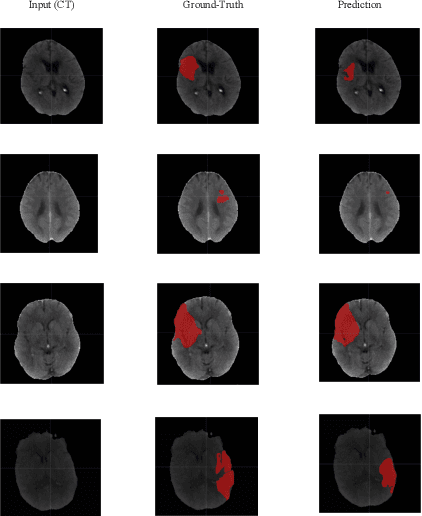

Abstract:Ischemic stroke occurs through a blockage of clogged blood vessels supplying blood to the brain. Segmentation of the stroke lesion is vital to improve diagnosis, outcome assessment and treatment planning. In this work, we propose a segmentation model with adversarial learning for ischemic lesion segmentation. We adopt U-Net with skip connection and dropout as segmentation baseline network and a fully connected network (FCN) as discriminator network. Discriminator network consists of 5 convolution layers followed by leaky-ReLU and an upsampling layer to rescale the output to the size of the input map. Training a segmentation network along with an adversarial network can detect and correct higher order inconsistencies between the segmentation maps produced by ground-truth and the Segmentor. We exploit three modalities (CT, DPWI, CBF) of acute computed tomography (CT) perfusion data provided in ISLES 2018 (Ischemic Stroke Lesion Segmentation) for ischemic lesion segmentation. Our model has achieved dice accuracy of 42.10% with the cross-validation of training and 39% with the testing data.